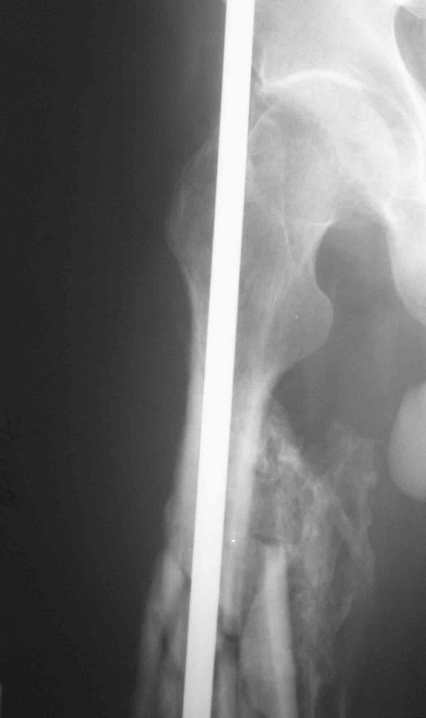

Re: 32- летний пациент с переломами обоих бедер после неудачного оперативного и консервативного лечения.

Иллюстрации к сообщению

Уважаемый Антон.Исходя из Вашего материального положения!! и наличия хорошего, грубого омозоления, равности длины конечностей и судя по снимкам не очень выраженной антекурвации, но выраженной контрактуры коленных суставов: чтоб не упустить время разработки суставов и активизировать больного, необходимо справа удалить стержень, рассверлить канал и произвести ЗИМО более толстым неблокир. стержнем т.к. на этом уровне можно получить устойчивый остеосинтез, после чего активизировать и дозированная, упорная ЛФК, а дальше после восстановления функции ,время покажеть.

Cyдя по представленным рентгенограммам оба бедра консолидированы. Необходима активная разработка движений в коленных суставах. Хотелось бы увидеть фотоснимки больного ( нижних конечностей спереди и сбоку). Если стержень мешает разработке движений то его надо удалить.

О происхождении такого запущенного случая- мой коллега работает экспертом ВТЭК и тянет в отделении и не такие казусы. Сегодня была сделана операция удален стержень из бедра и установлен стержневой аппарат из 2 опор, слева подвижности не наблюдалось, продолжается ЛФК. При необходимости позднее будет выполнена надмыщелковая корригирующая остеотомия. Спасибо всем за советы.